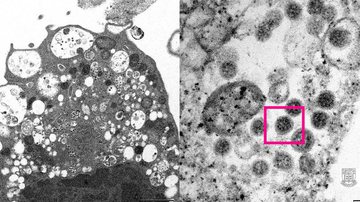

Faculdade de Medicina da Universidade de Hong Kong

Há ainda, segundo a pasta, sete casos suspeitos da variante ômicron em investigação  |   Bnews - Divulgação Faculdade de Medicina da Universidade de Hong Kong